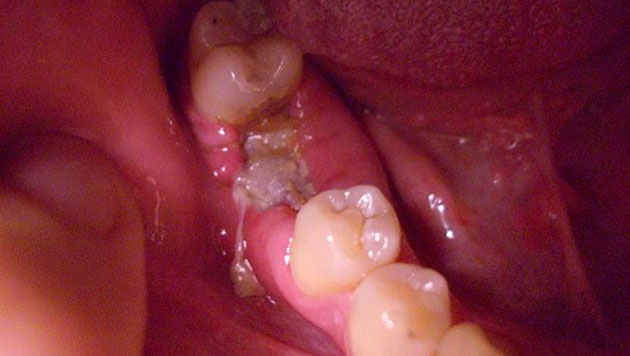

Нередко болит скула на лице из-за стоматологических патологий.

Провоцируют боль в скулах заболевания зубов:

- кариес;

- пульпит;

- периодонтит;

- абсцесс десны;

- флегмона.

Чаще всего причиной становится кариес. При отсутствии лечения заболевание нередко приводит к появлению пульпита и других осложнений.

Причина боли №1: стоматологические заболевания

Отдавать болезненными ощущениями в скулу может даже тогда, когда имеет место обычный кариес или пульпит, периодонтит, стоматит или альвеолит, возникший вследствие удаления зуба. Ведь все органы челюстно-лицевого аппарата расположены в опасной близости друг от друга.

Хуже, когда простое стоматологическое заболевание долго оставалось невылеченным и инфекция начала распространяться дальше, дойдя до скуловой области лица. Тогда у вас уже могут болеть скулы от более серьезной патологии – остеомиелита. Заболевание поражает костную ткань челюсти, вызывая ее нагноение и некроз, сопровождается общим ухудшением самочувствия, поднимается температура тела, лицо может опухнуть и деформироваться.